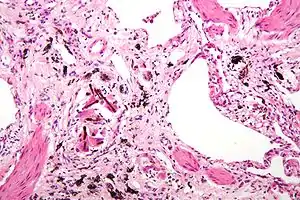

Asbestosis is the scarring of lung tissue (beginning around terminal bronchioles and alveolar ducts and extending into the alveolar walls) resulting from the inhalation of asbestos fibers. There are two types of fibers: amphibole (thin and straight) and serpentine (curly). All forms of asbestos fibers are responsible for human disease as they are able to penetrate deeply into the lungs. When such fibers reach the alveoli (air sacs) in the lung, where oxygen is transferred into the blood, the foreign bodies (asbestos fibers) cause the activation of the lungs' local immune system and provoke an inflammatory reaction dominated by lung macrophages that respond to chemotactic factors activated by the fibers.[19] This inflammatory reaction can be described as chronic rather than acute, with a slow ongoing progression of the immune system attempting to eliminate the foreign fibers. Macrophages phagocytose (ingest) the fibers and stimulate fibroblasts to deposit connective tissue. Due to the asbestos fibers' natural resistance to digestion, some macrophages are killed and others release inflammatory chemical signals, attracting further lung macrophages and fibrolastic cells that synthesize fibrous scar tissue, which eventually becomes diffuse and can progress in heavily exposed individuals. This tissue can be seen microscopically soon after exposure in animal models. Some asbestos fibers become layered by an iron-containing proteinaceous material (ferruginous body) in cases of heavy exposure where about 10% of the fibers become coated. Most inhaled asbestos fibers remain uncoated. About 20% of the inhaled fibers are transported by cytoskeletal components of the alveolar epithelium to the interstitial compartment of the lung where they interact with macrophages and mesenchymal cells. The cytokines, transforming growth factor beta and tumor necrosis factor alpha, appear to play major roles in the development of scarring inasmuch as the process can be blocked in animal models by preventing the expression of the growth factors.[20][21] The result is fibrosis in the interstitial space, thus asbestosis. This fibrotic scarring causes alveolar walls to thicken, which reduces elasticity and gas diffusion, reducing oxygen transfer to the blood as well as the removal of carbon dioxide. This can result in shortness of breath, a common symptom exhibited by individuals with asbestosis.[22]

Extensive fibrosis of pleura and lung parenchyma.

The arrow points to an uncoated segment of asbestos fiber in this ferruginous body.

Severe pleural fibrosis with focal calcification.

The black arrows point to ferrugionous bodies that are located at the periphery of a focus of non-small cell lung carcinoma, NOS.

61 yr old working industrially with asbestos for decades.